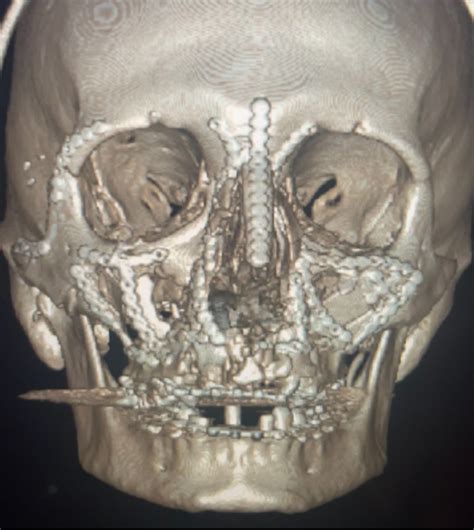

Treating a Lefort III fracture is a highly technical process involving specialized maxillofacial and neurosurgical teams. The goal of surgery is to achieve anatomical reduction, ensuring that the facial bones are returned to their original position and fixed securely. Surgeons typically utilize open reduction and internal fixation (ORIF) techniques.

• Access Incisions: Surgeons often use coronal or bicoronal incisions (hidden behind the hairline) to expose the zygomatic arches and the top of the facial skeleton without visible scarring.

• Bone Plating: Titanium mini-plates and screws are used to bridge the fracture gaps, effectively pinning the midface back to the stable, non-fractured parts of the cranium.

• Bone Grafting: In cases of significant comminution, where bones are shattered into many pieces, bone grafts may be necessary to provide the required volume and stability for healing.